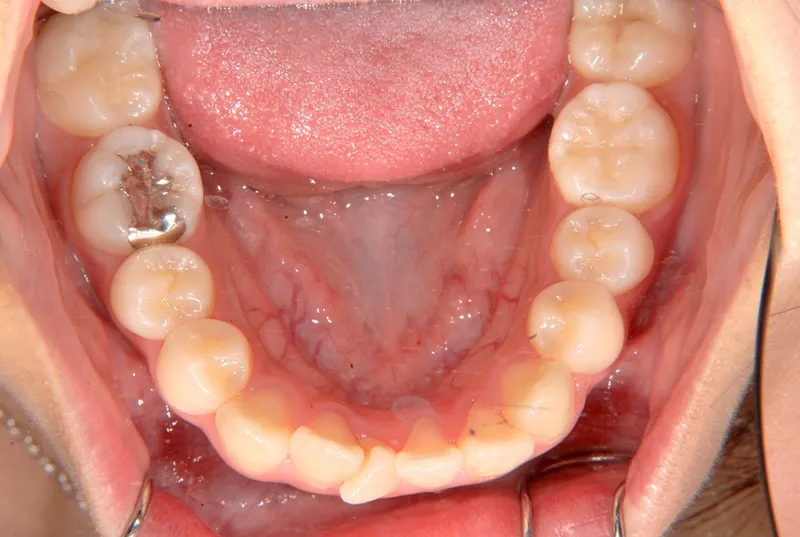

初診時年齢 中学生 (女性) 主訴 八重歯・噛めない

診断名 叢生・開咬 装置名

状態 ガタガタ・でこぼこに生えている(叢生)

八重歯(叢生)

前歯で噛めない(開咬/オープンバイト)

歯ががたがたで、噛み合わせもずれています。